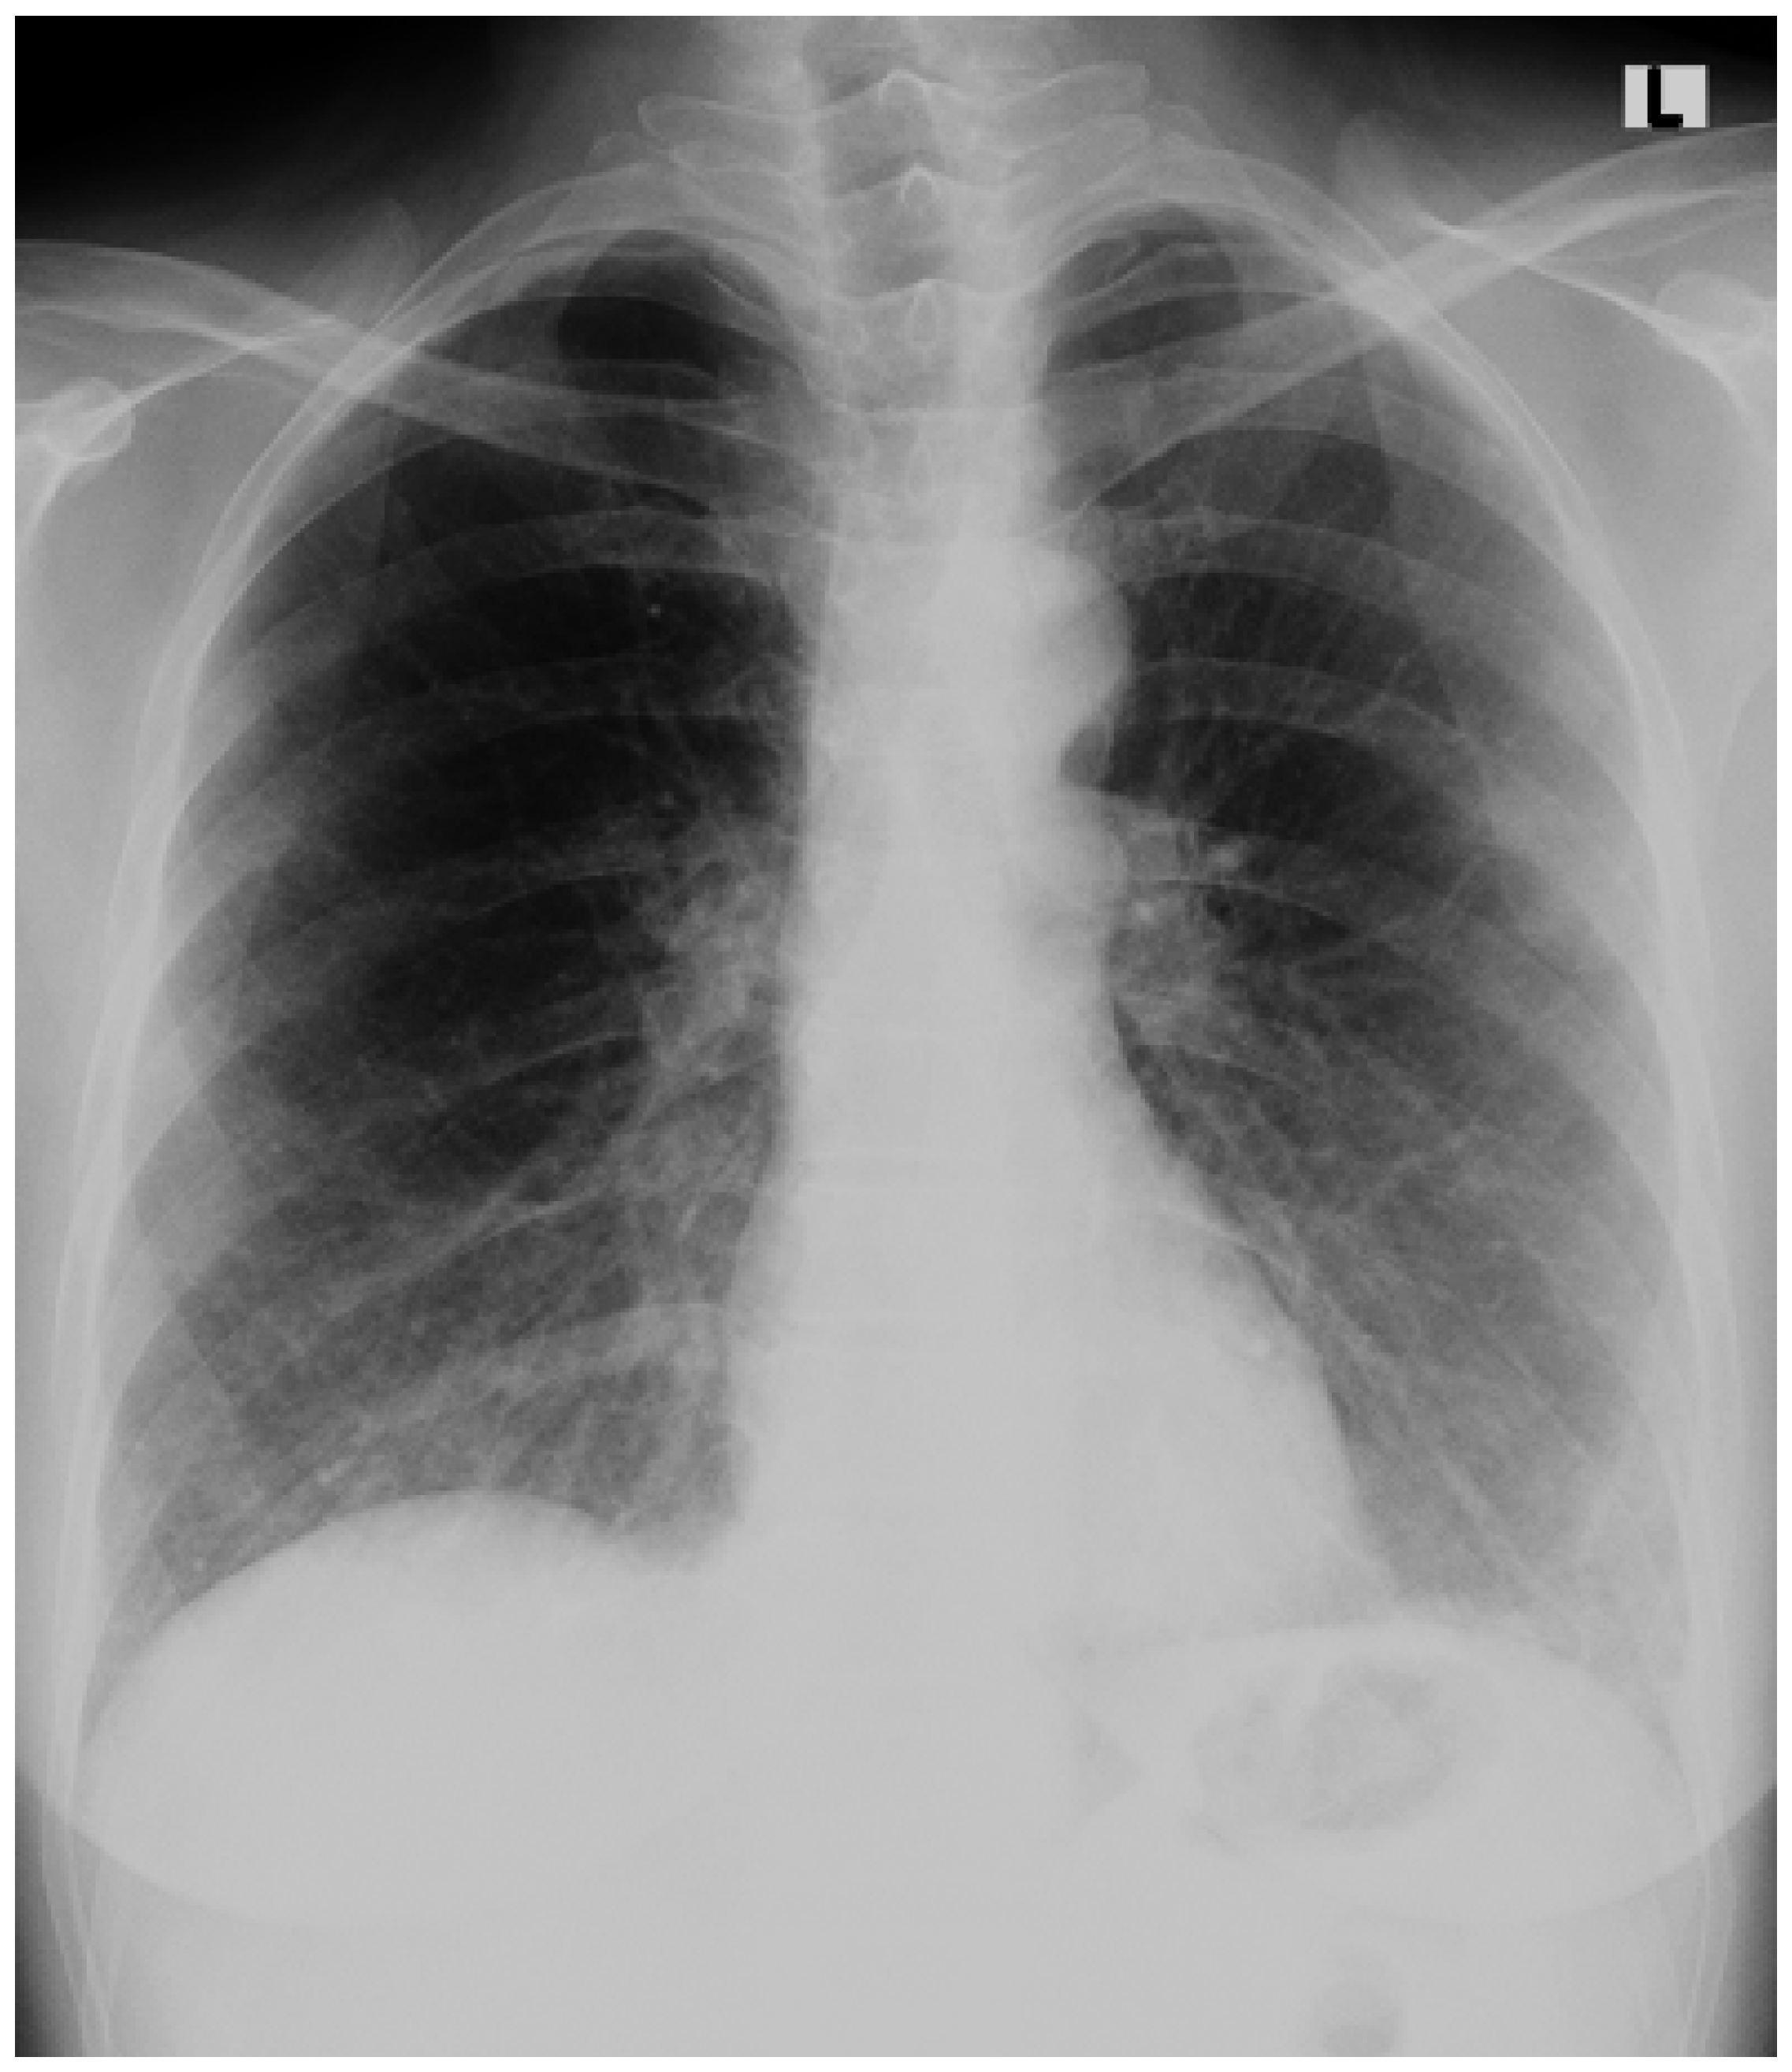

An Accidental Overdose of Colchicine Results in Immediate Recovery of the Patient

Discussion